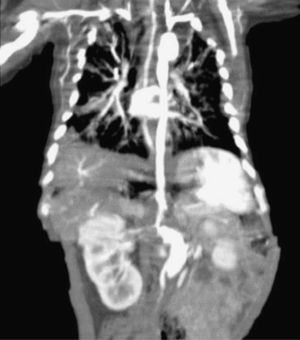

While performing the first echodopplercardiogram, a dilated descending aorta was observed, corroborated by a postsurgical repair of the PDA echocardiography, with an aneurysm of the aortic arch distal to the subclavian artery and the presence of thrombus 4cm×3cm at the mouth of superior vena cava; an angiotomography demonstrated an aortic aneurism, a probable aortic coarctation, plus an abdominal aortic aneurysm (Fig. 1). At diagnosis, the patient had a normal platelet and white blood cell count, anemia, hypocomplementemia at the expense of C3, increased factor VIII and positive PCR.

When control echocardiograms were performed for the underlying cardiac disease, aortic dilatation was noted, being more evident in the 3rd week of life; because of this finding, we opted to confirm it through a CT angiography (Fig. 2)